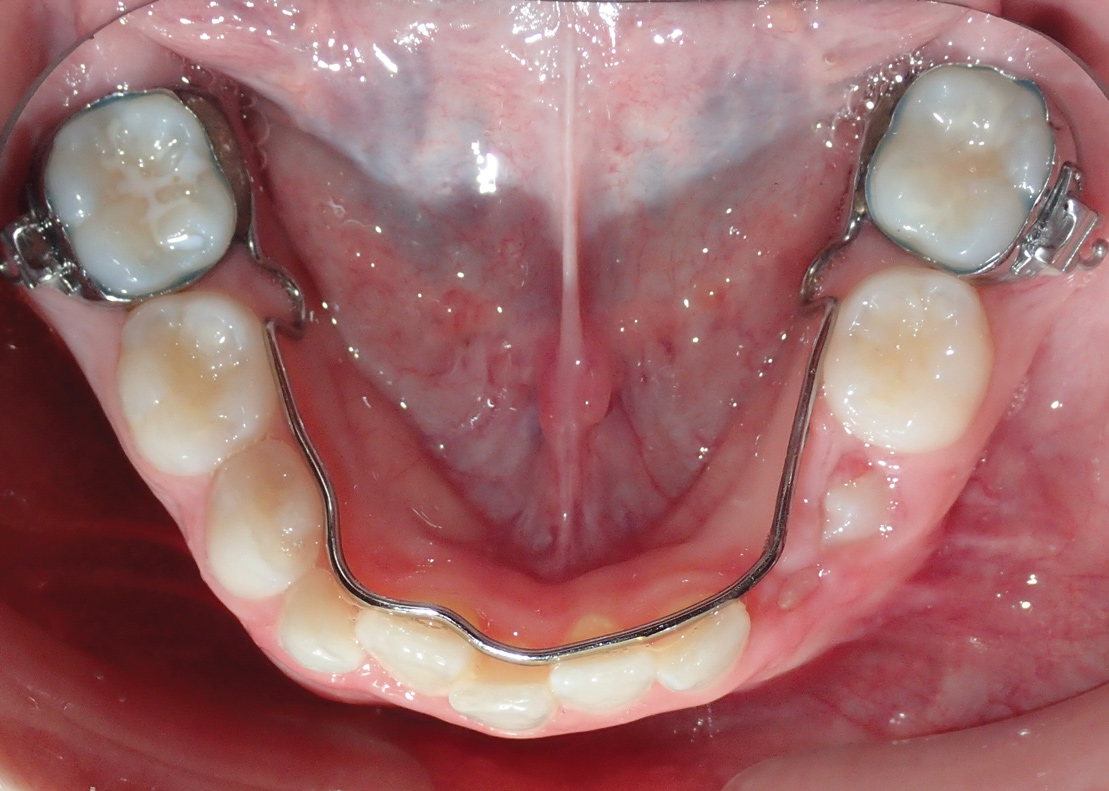

Fig 12. Palatal crib used to passively close bite and break thumb-sucking habit, at delivery (Fig 12), 6 weeks (Fig 13), and 12 weeks (Fig 14).

Figure 12

Fig 13. Palatal crib used to passively close bite and break thumb-sucking habit, at delivery (Fig 12), 6 weeks (Fig 13), and 12 weeks (Fig 14).

Figure 13

Fig 14. Palatal crib used to passively close bite and break thumb-sucking habit, at delivery (Fig 12), 6 weeks (Fig 13), and 12 weeks (Fig 14).

Figure 14

Tongue and thumb pressures also contribute to a high-vaulted palate, which can lead to mouth breathing (Figure 11).31 Additional risks exist for infection and callus development on the thumb. Ideally, the child should quit this habit by age 4, before permanent occlusal changes develop.32 Quitting can be achieved through positive reinforcement and by offering the child comfort during thumb-sucking triggers. The use of bitterants (eg, Mavala Stop, Thum, Control-It!), which are painted on or rubbed into the thumb, is another option.33 A habit breaker appliance may also be utilized if these techniques are unsuccessful. Devices such as a palatal crib, rake, or bluegrass appliance interfere with the thumb and tongue habits and allow the bite to passively close.34 The author recommends utilizing a habit breaker appliance for 6 to 9 months and maintaining reinforcement for a few months once the habit is eliminated (Figure 12 through Figure 14).